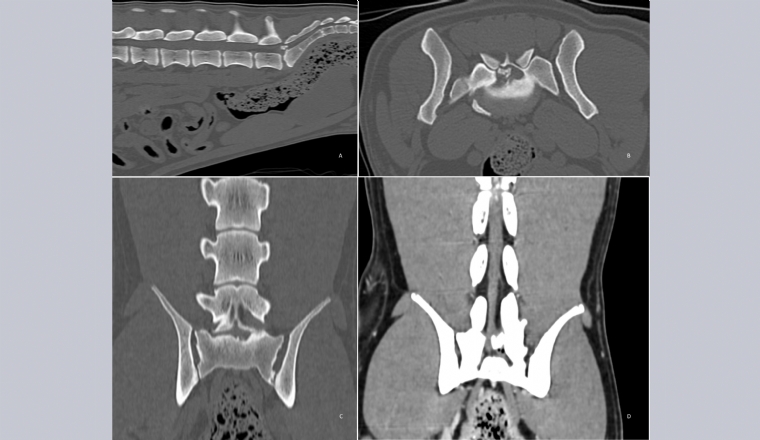

Mercredi 14 Juin 2023 Animaux de compagnieExamen tomodensitométrique : reconstructions sagittale, transverse et dorsale de la colonne lombosacrée (fenêtre osseuse (A, B et C) et tissus mous (D)).

Une chienne berger allemand de 5 ans est présentée pour des douleurs lors de sauts et à la manipulation de la jonction lombosacrée ainsi qu'un port de queue bas.